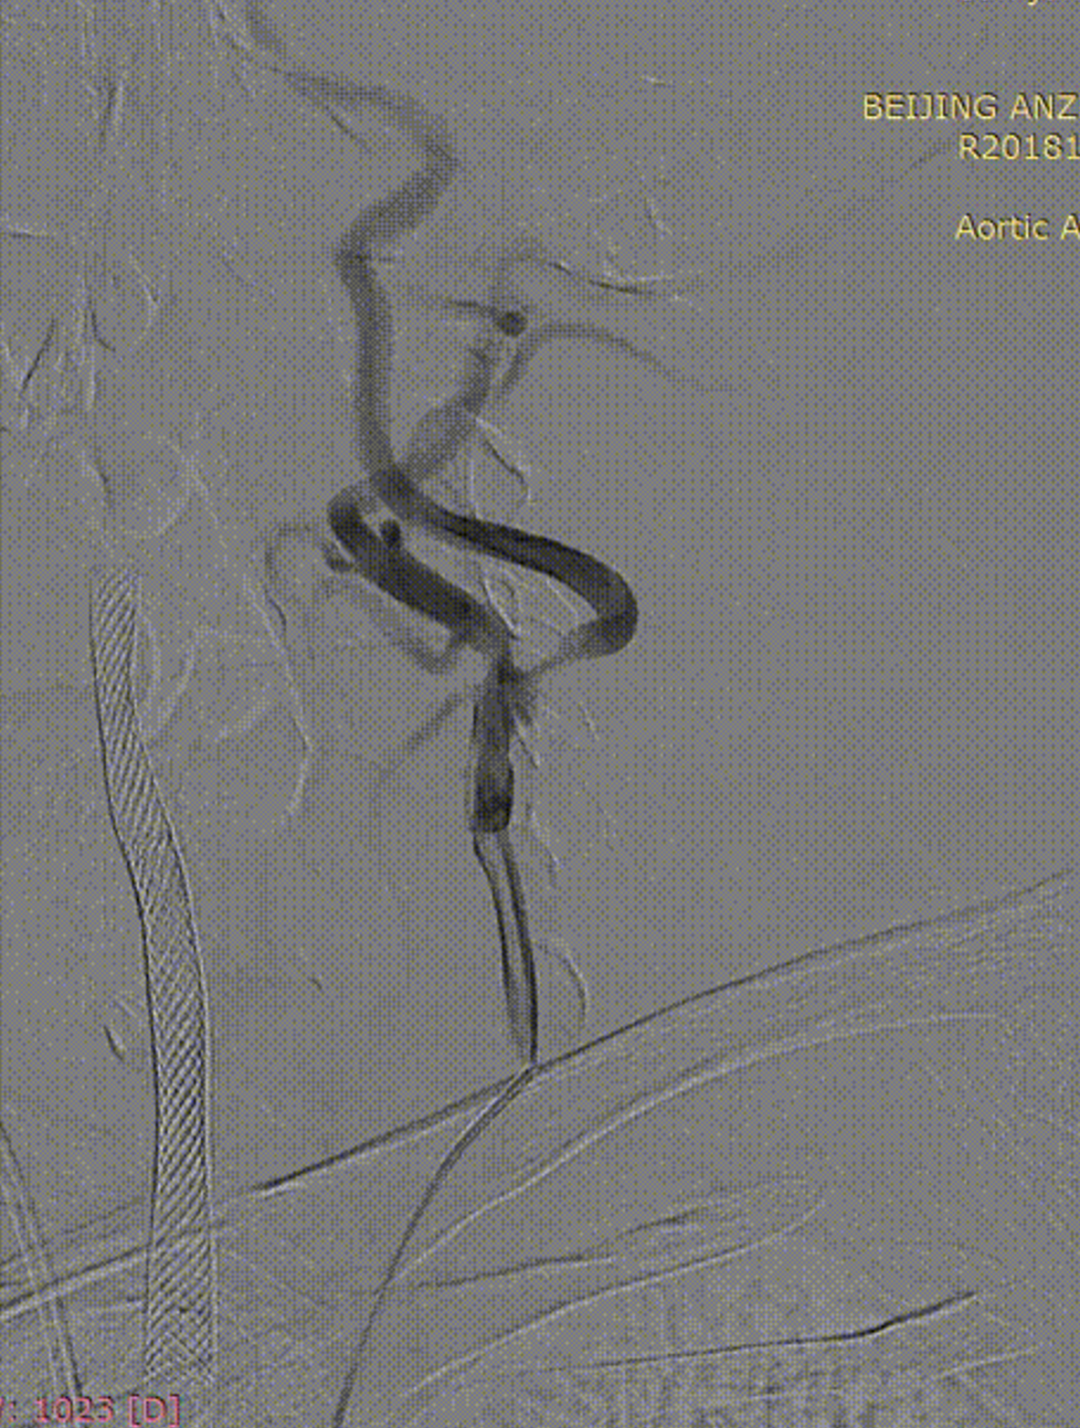

病例2:52岁男性,发作性胸痛2年,体检发现双侧颈动脉狭窄,冠脉情况严重,先行PCI,后行双侧CAS,先右后左,术后复查颈动脉支架通畅。

右侧术前

右侧术后

左侧术前

左侧术后